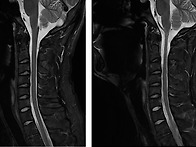

살고싶다 님의 경추, 흉추..

엔젤 25.11.22경추부위는 심하지 않습니다.자잘한 디스크가 있는데 심하지 않고, ..